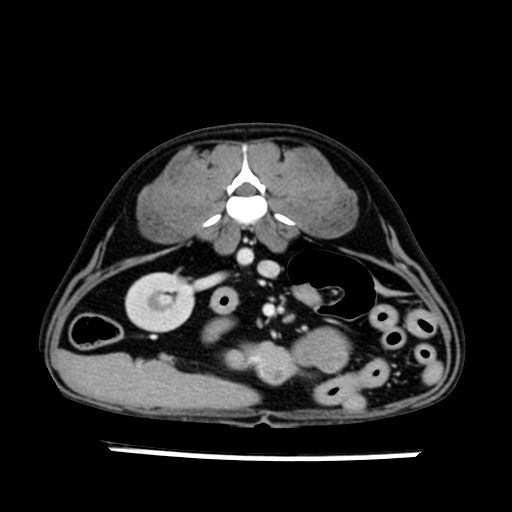

prescritto esame TAC

sequenza immagini limitata al fegato reni e surreni

le immagini ecografiche rispetto alla tac datano circa 7 mesi prima ,le surrenali sono normali nonostante il test acth sia risultato positivo .all’esame TAC dopo diversi mesi risultano aumentate armonicamente nel volume e si individua un forte sospetto di adenoma ipofisario .

sospetto adenoma ipofisario vs. meno probabilmente meningioma della base; intertiziopatia polmonare; lesione espansiva epatica, verosimilmente del lobo laterale sinistro, di sospetta natura neoplastica; lesioni spleniche di natura da definire; iperplasia/ipertrofia delle ghiandole surrenali, bilateralmente; vertebra di transizione del rachide toracico; tenosinovite cronica del muscolo bicipite brachiale di destra.